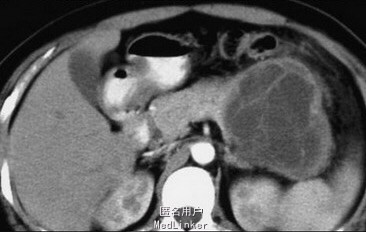

女性,48岁,左腹胀痛3个月。

CT表现:胰腺体尾部囊性占位性病变,体积大,边界清楚;周边囊壁及内部的不规则分隔、壁结节,增强扫描均呈渐进中度强化。

行开腹胰体尾联合脾脏切除,术后病理: 胰腺粘液性囊腺瘤